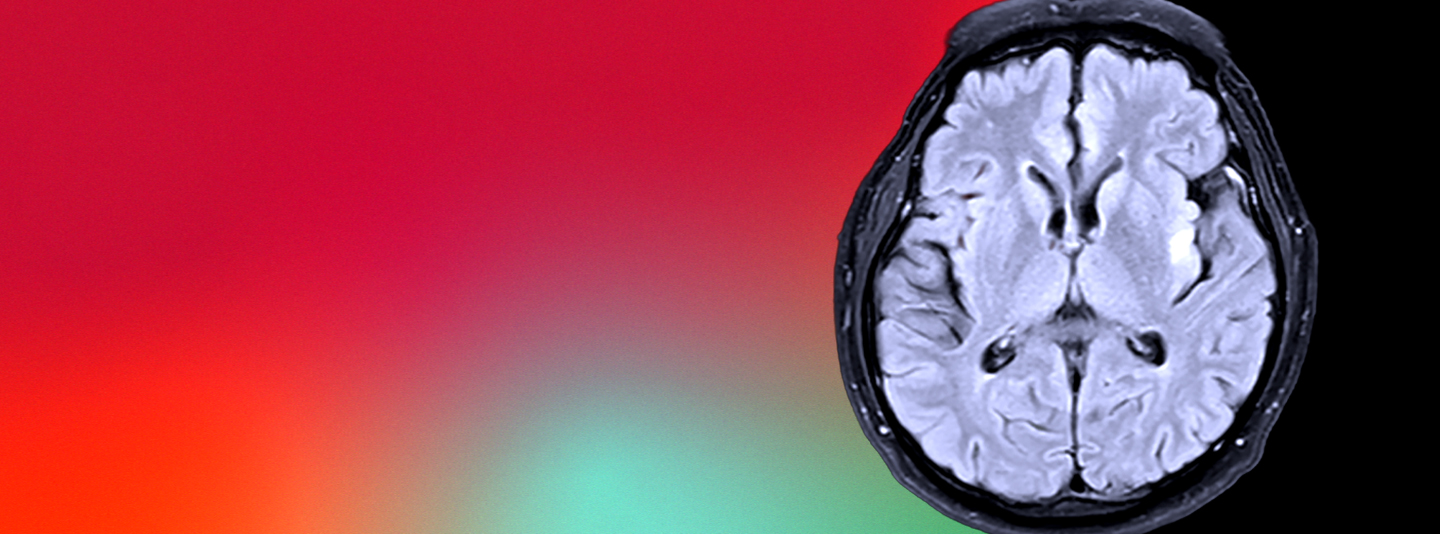

What if we can stop Alzheimer’s before it starts?

This disease steals the moments that make us who we are and the memories we share. That’s why we attack Alzheimer’s from every angle — because every breakthrough means more time, more hope and more moments together for families who can’t wait.